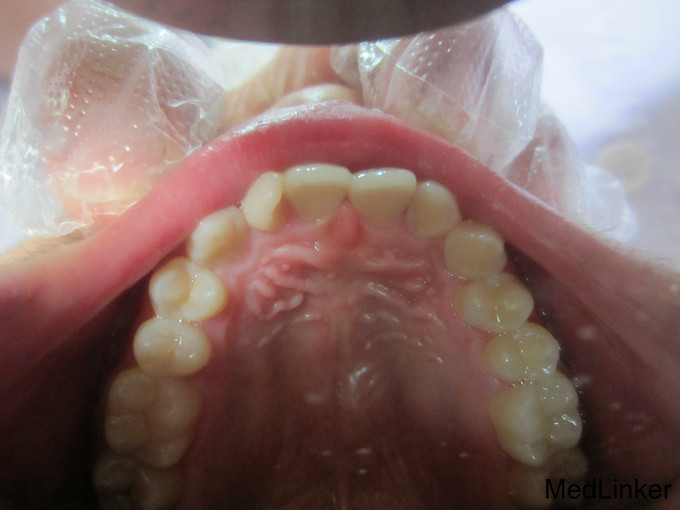

检 查:双侧颞下颌关节开口弹响,开口度一度; 模型测量分析:3度深覆合,上下颌轻度拥挤,spee曲线陡峭,上下颌尖牙尖锐、宽度较小,; 头 颅 侧位片:下颌平面角低角,下颌后缩,余正常; 辅 查:曲面断层片、头颅侧位片,双侧颞下颌关节片

诊断:深覆合、下颌后缩导致颞下颌关节负担加重,引起关节紊乱 治疗:一期:制作合平面导板,戴用一月后关节症状减轻,确定病因; 二期:带用固定矫治器,首先排齐上颌4个月,之后配合平面导板及摇椅弓排齐整平下颌5个月,调整上下颌咬合关系3个月,精细调整2个月,保 持1个月后拆除矫治器,患者自觉关节症状明显好转,制作保持器保持。